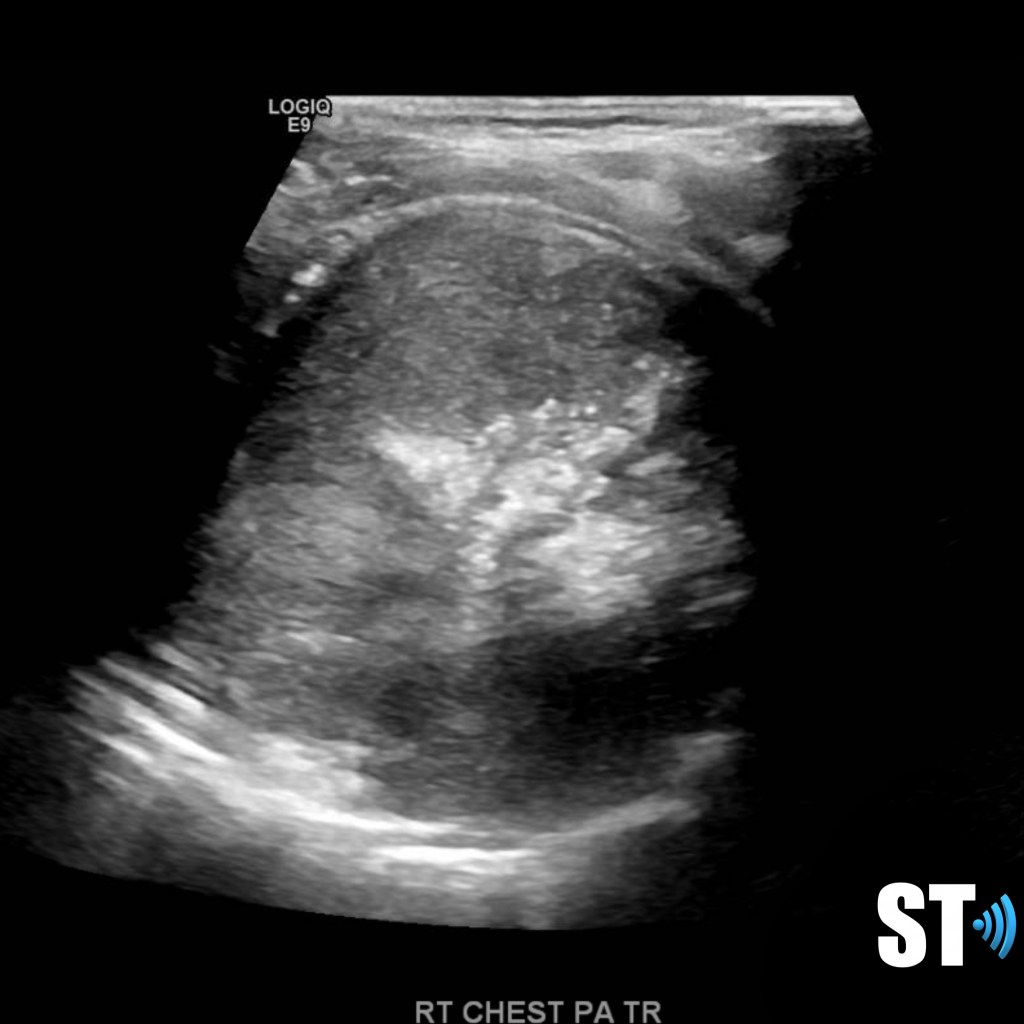

Right sided sarcoma with pleural effusion

Right chest sarcoma with pleural effusion